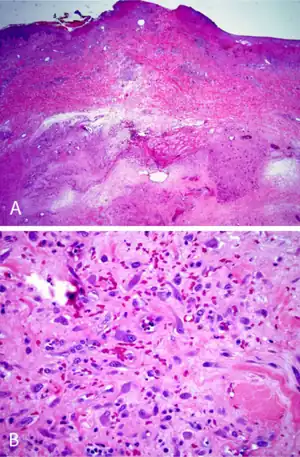

On gross examination, IF tumors are typically white-yellow masses with central necrosis (i.e. areas of dead or dying cells), and areas containing cysts and/or old, dried hemorrhages.[6] The tumors are often poorly circumscribed, have an infiltrative appearance, may be multinodular, and lie in subcutaneous tissue but may also involve the dermal layer of the skin[8] and/or the reticular dermis.[6] Microscopic histopathological studies of IF tissues report the characteristic presence of a distinct zonal appearance, i.e. the presence of central zones of fibrinoid necrosis and areas of cyst-laden necrosis in a hypocellular background surrounding by a zone of granulation tissue (i.e. connective tissue containing microscopic blood vessels) populated by atypical, swollen fibroblasts, myofibroblasts, and/or macrophages.[4]